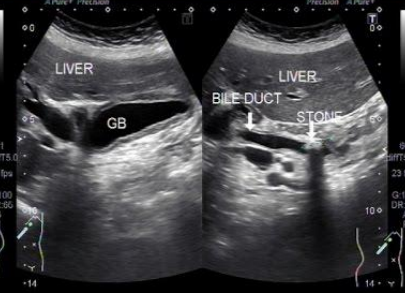

Describe this image

Dx:

Gallbladder in both the longitudinal and transverse planes with low level echoes suggestive of sludge and distention (gallbladder hydrops).

Dx: Likely diagnosis is choledocholithiasis

Dx?